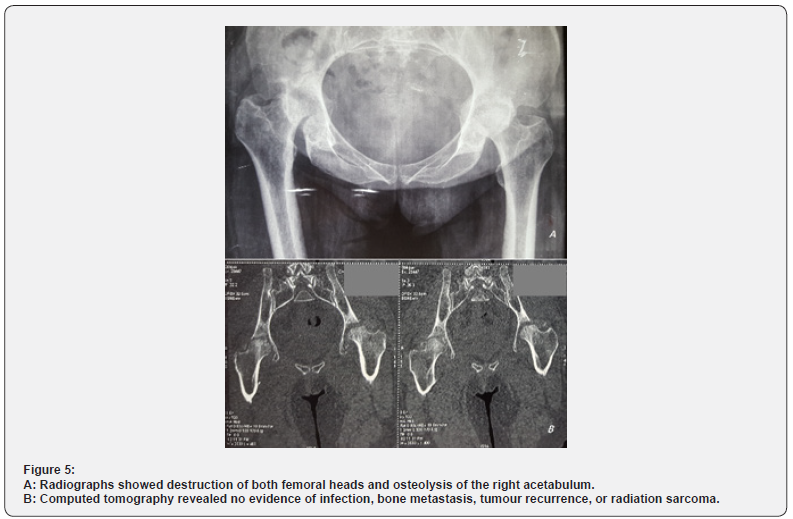

Radiographs showed destruction of both femoral heads and osteolysis of the right acetabulum (Figure 5a). Computed tomography revealed no evidence of infection, bone metastasis, tumour recurrence, or radiation sarcoma (Figure 5b). The CT‑guided biopsy revealed no evidence of malignancy in the right hip. The patient underwent a total hip arthroplasty by a cemented femoral and acetabular component. Pathological examination revealed no signs of malignancy. At eight months follow-up she had no pain over the right hip and could walk without sticks, the Postel Merle d’Aubigné (PMA) score was 15.